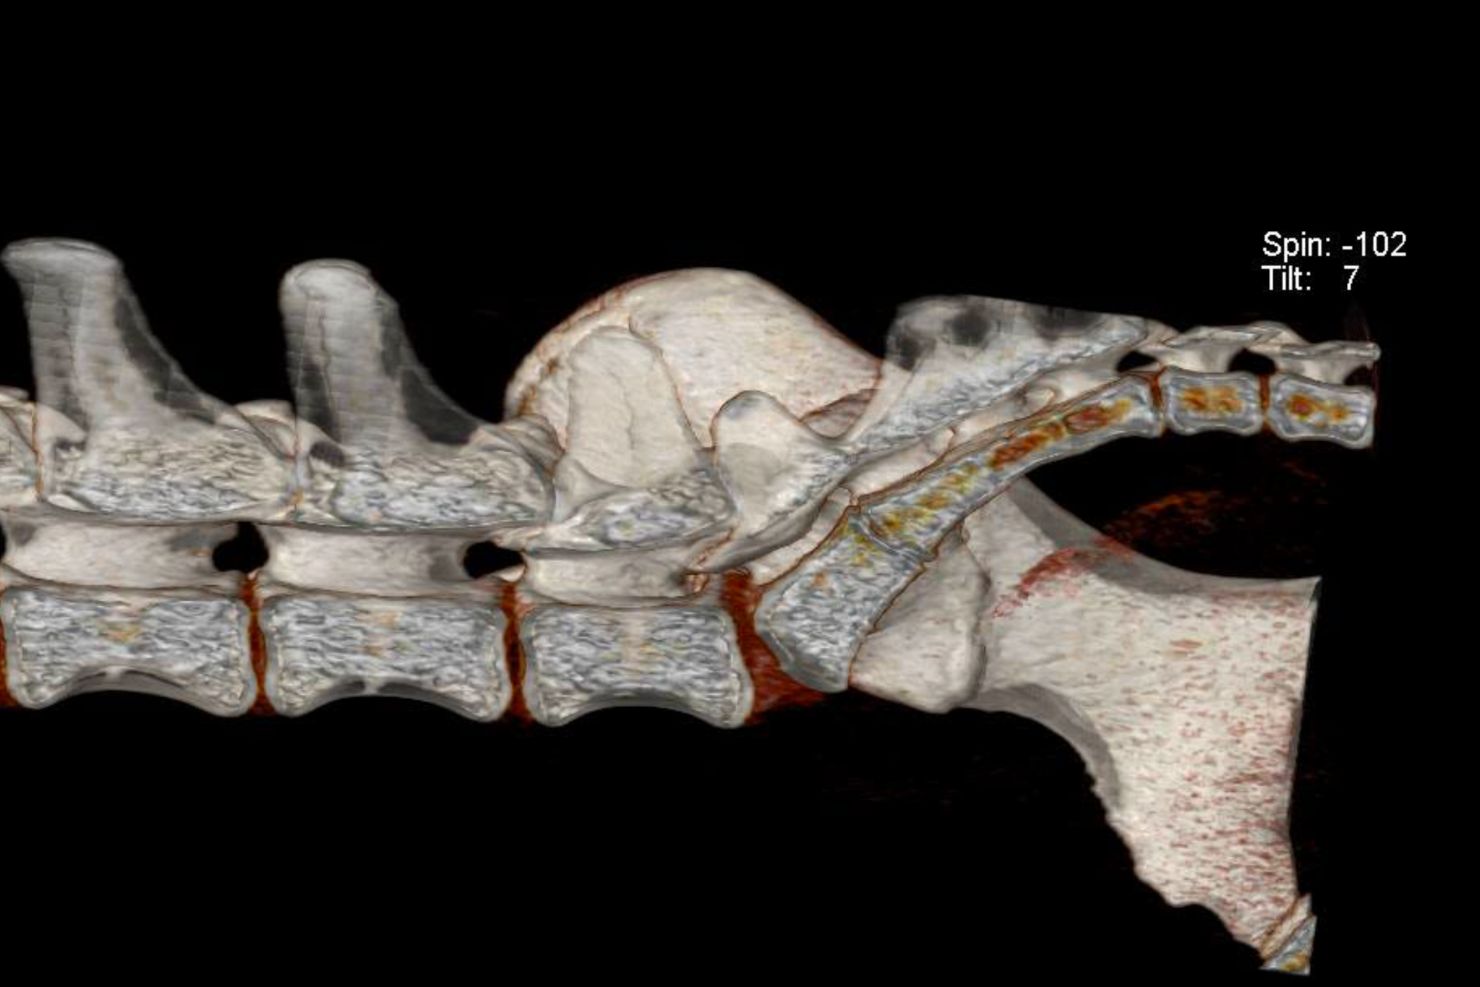

Zentral ist für mich lumbosakraler Druckschmerz bei Palpation in Kombination mit dem Vorstellungsgrund „Möchte nicht mehr springen / Stiegen steigen / ballspielen“ oder einer leichten Lahmheit. Wichtig ist es, sowohl eine neurologische als auch eine orthopädische Untersuchung durchzuführen, da die Symptome eben nicht charakteristisch für eine neurologische Erkrankung sind. Der Ausschluss von orthopädischen Problemen ist sehr wichtig – da ältere Patienten betroffen sind, kann es sein, dass beide Probleme vorliegen. Das erschwert die Diagnosestellung und man braucht weitere Schritte zur Bestätigung. Röntgenbilder können die Verdachtsdiagnose erhärten, aber nicht bestätigen. Um sie zu bestätigen, braucht man schnittbildgebende Verfahren wie etwa CT oder MRT.

Die chirurgischen Lösungsansätze teilen sich in zwei Bereiche auf: Dekompression oder Stabilisation. Dekompression entlastet die komprimierte Struktur. Bei lateraler Nervenkompression kann zum Beispiel die bekannte Foraminotomie Erfolg bringen.